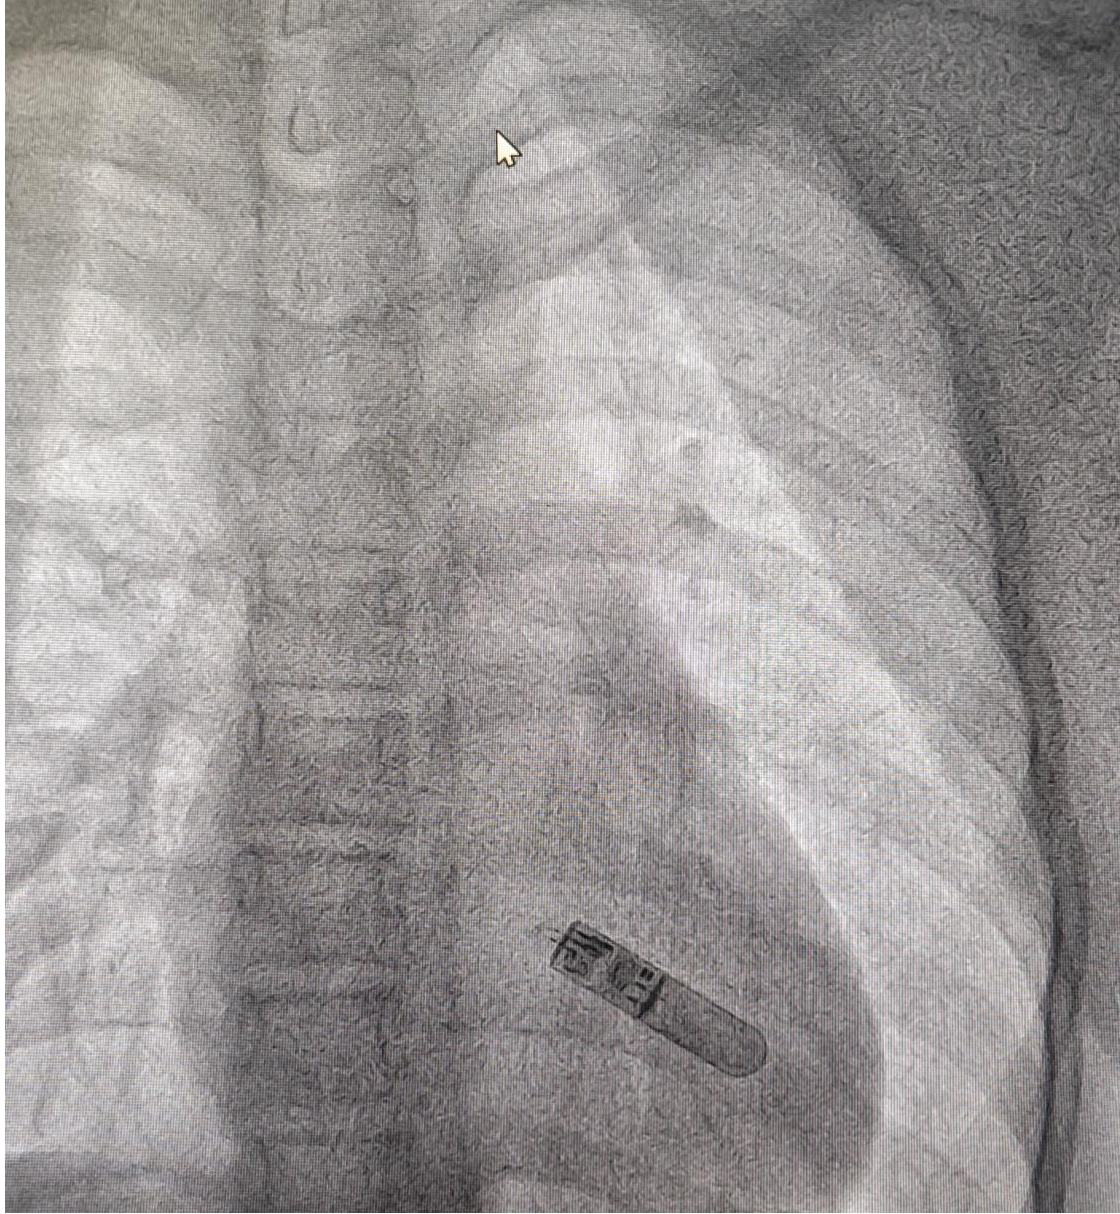

手术由湖南省儿童医院陈智主任团队实施,消毒铺巾后,在局部麻醉下,王野峰副主任医师借助专用导引系统将Assert-IQ精准定位至患者左胸第4肋间、距胸骨左缘2cm皮下组织。整个植入过程仅需5分钟左右,切口不足1厘米,出血量不足1ml。术中即刻程控显示,设备R波振幅达0.53mV,信号采集清晰度达临床诊断金标准,远程连接测试同步完成。"患者术后即可下床活动,次日顺利出院,真正实现了微创无感、即植即用。

植入过程及术中影像